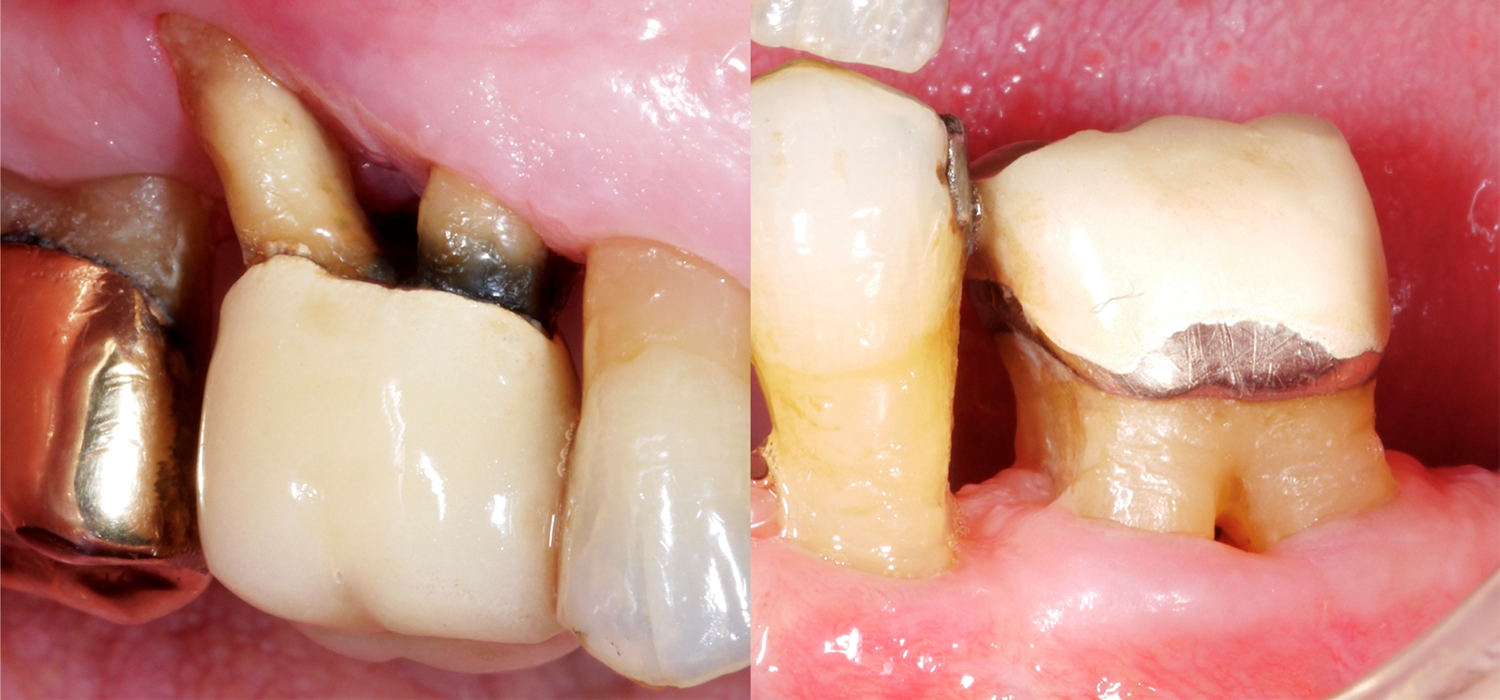

Wenn man nun an die Zähne denkt, dann sind natürlich mehrwurzelige Zähne oft viel schwieriger zu therapieren, im Speziellen, wenn sie einen Furkationsbefall aufweisen. Warum ist der Furkationsbereich so anspruchsvoll? Der Zugang für die mechanische Reinigung der Wurzeloberfläche ist im Vergleich zu einwurzeligen Zähnen viel schwieriger, der Furkationseingang kann oft sehr klein/schmal sein, und zusätzlich kann es noch anatomische Besonderheiten, wie beispielsweise Schmelzprojektionen, geben.

In einer kürzlich publizierten Arbeit aus Frankfurt (Eickholz 2021) wurden im Speziellen Zähne mit einem durchgängigen Furkationsbefall untersucht. Sie untersuchten insgesamt 265 Zähne mit einem durchgängigen Furkationsbefall von 160 PatientInnen; alle PatientInnen waren seit mindestens 5 Jahre in parodontaler Erhaltungstherapie. Folgende wichtige Punkte sollten wir basierend auf diesen Daten berücksichtigen:

- Zähne mit Furkationsbefall Grad III gehen häufiger verloren als beispielsweise einwurzelige Zähne und nach ca. 10 Jahren parodontaler Erhaltungstherapie müssen wir damit rechnen, dass ca. ein Drittel dieser Zähne extrahiert wurde. Das bedeutet aber zugleich auch, dass zwei Drittel dieser parodontal schwer kompromittierten Zähne nach wie vor im Mund sind!

- Die Gründe für eine Extraktion können bunt gemischt sein – von parodontalen Problemen, bis zu Karies und/oder prothetischen Problemen.

- Folgende Risikofaktoren für einen Verlust wurden für Zähne mit einem durchgängigen Furkationsbefall identifiziert: Ein höherer Knochenverlust zu Beginn der Therapie und höhere Sondierungstiefen zu Beginn der Erhaltungstherapie!